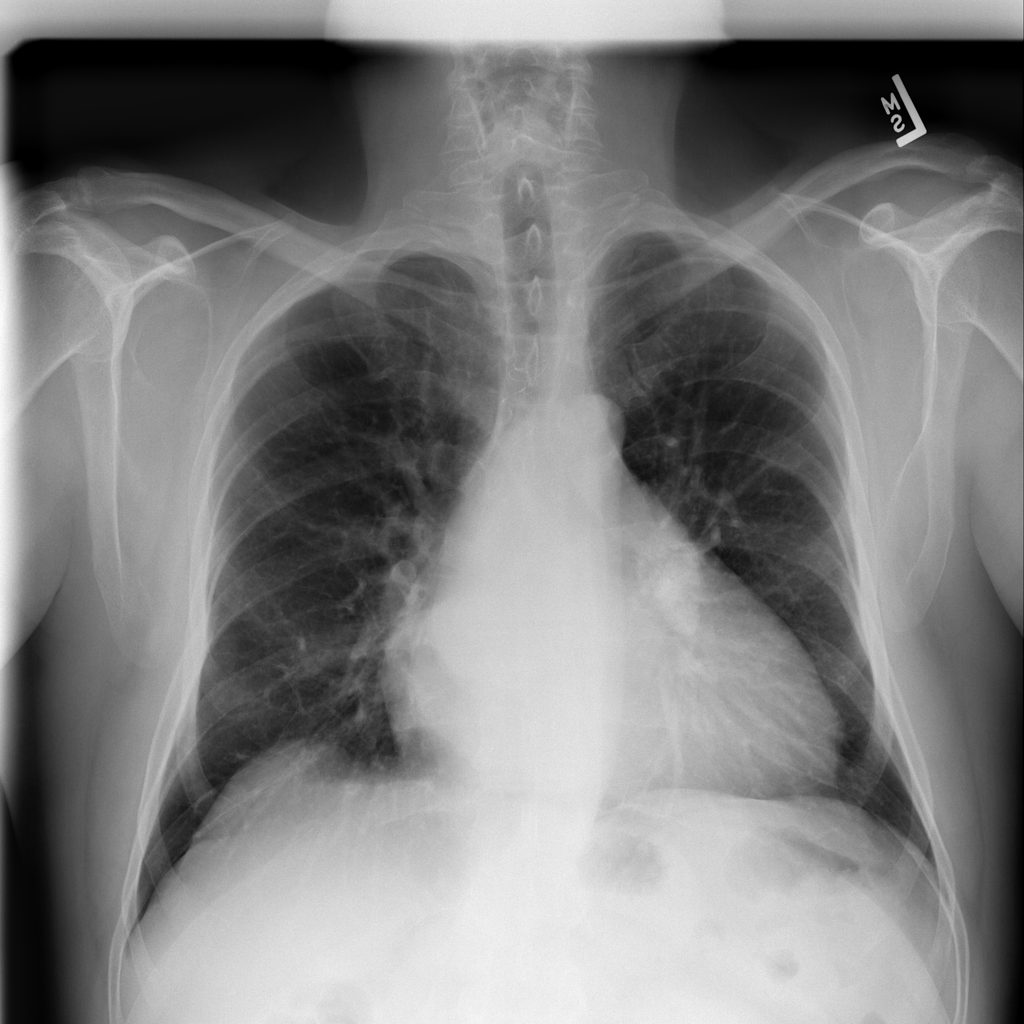

Disease predictions: A probability indicating how likely the image contains the disease. 50% means the network is not sure.

This is a prototype system for diagnosing

chest X-Rays using NN's (Neural Networks). All processing is done on your

device and images are not sent to any server. By continuing, you

assume any liability for using the system to diagnosis patients. Two NN models

(total size:100MB) will be downloaded to your browser.